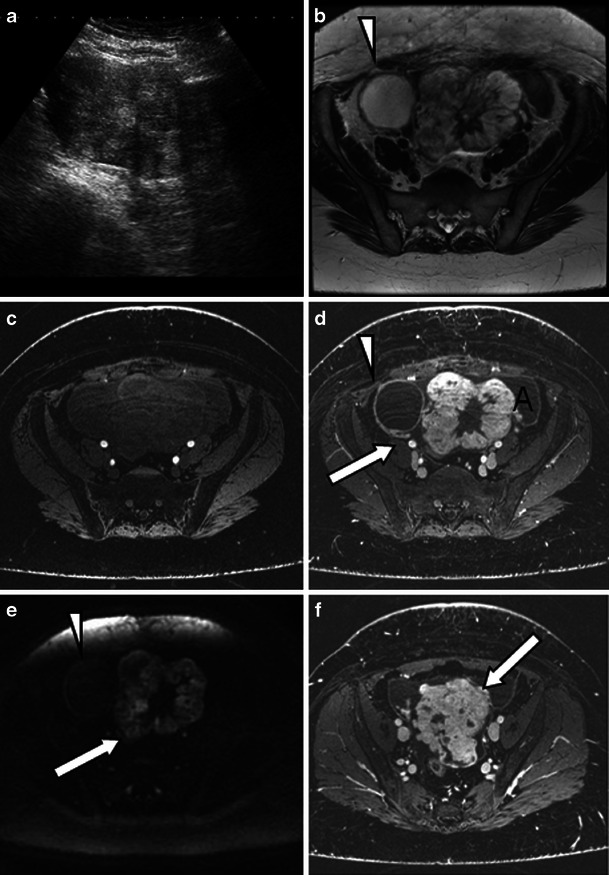

Fig. 9.

Malignant struma arising from the left ovary in a 40-year-old woman presenting with abdominal distension and lower abdominal pain. CA-125 levels were elevated at 1,075 kU/l (normal value <12 kU/l). a Ultrasound shows a mixed solid cystic mass with predominantly solid features. On the 3-T T2-weighted high-resolution (b), unenhanced (c) and enhanced (d, f) T1 fat-saturated LAVA and diffusion-weighted images b = 1,200 mm/s2 (e), imaging features resemble a mucinous cystadenocarcinoma. d, e The lacy pattern caused by the enhancing solid elements (representing thyroid tissue) can be seen on T1 post-contrast imaging (d) and diffusion imaging (e) might be the only feature to suggest a struma. d, f Ascites is present (A) as well as extracapsular extension which is seen as tumour nodules on the capsular surface (arrow). d, e Some contrast medium uptake is shown in the tissues between the ovary and pelvic sidewall on the right (arrow). b, d, e A simple cyst arising from the right ovary does not present with restricted diffusion (arrowheads)